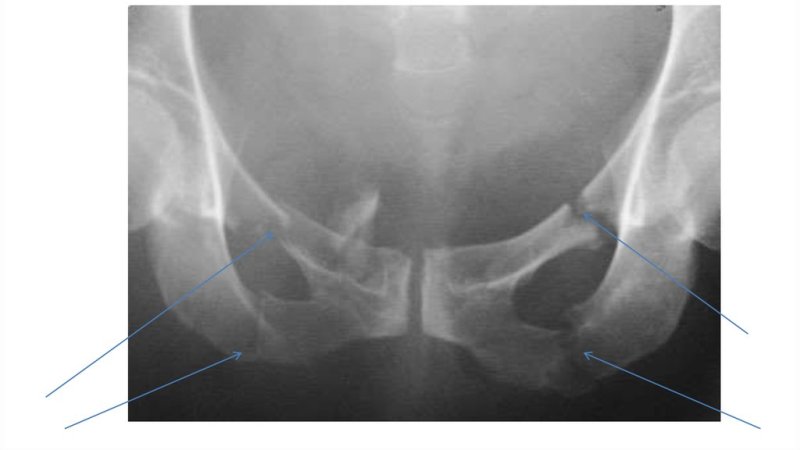

Окостенение проходит в четыре этапа, которые приходятся на разные этапы развития ребенка. Начальные участки роста костной ткани выявляются уже у новорожденных детей. При проведении рентгенологического исследования, у ребенка после рождения удается выявить три отдельных кости, которые отделены друг от друга значительной прослойкой соединительной и хрящевой ткани. На данном этапе развития, структура таза еще не сформирована, а ветвь седалищной и лобковой кости не соединены.

Второй этап окостенения приходится на 7-8 лет. На рентгенограммах выявляется соединение друг с другом ветвей, что свидетельствует о начале формирования целостного тазового кольца.

Третий этап приходится на 14-15 лет и связан с увеличением количества половых гормонов и гормона роста в крови. Он проявляется формированием вертлужной впадины, которая участвует в образовании тазобедренного сустава, совместно с головкой бедренной кости.

В возрасте от 10 до 20 лет начинается активное окостенение бугорков на поверхности кости. Связано это с повышением нагрузки на связки и сухожилия мышц, прикрепляющихся к ним. Окончательный этап окостенения приходится на 20-25 летний возраст. В это время кости таза окончательно сливаются друг с другом, образуя монолитную структуру. С этого времени, анатомическое строение седалищной кости не изменяется.